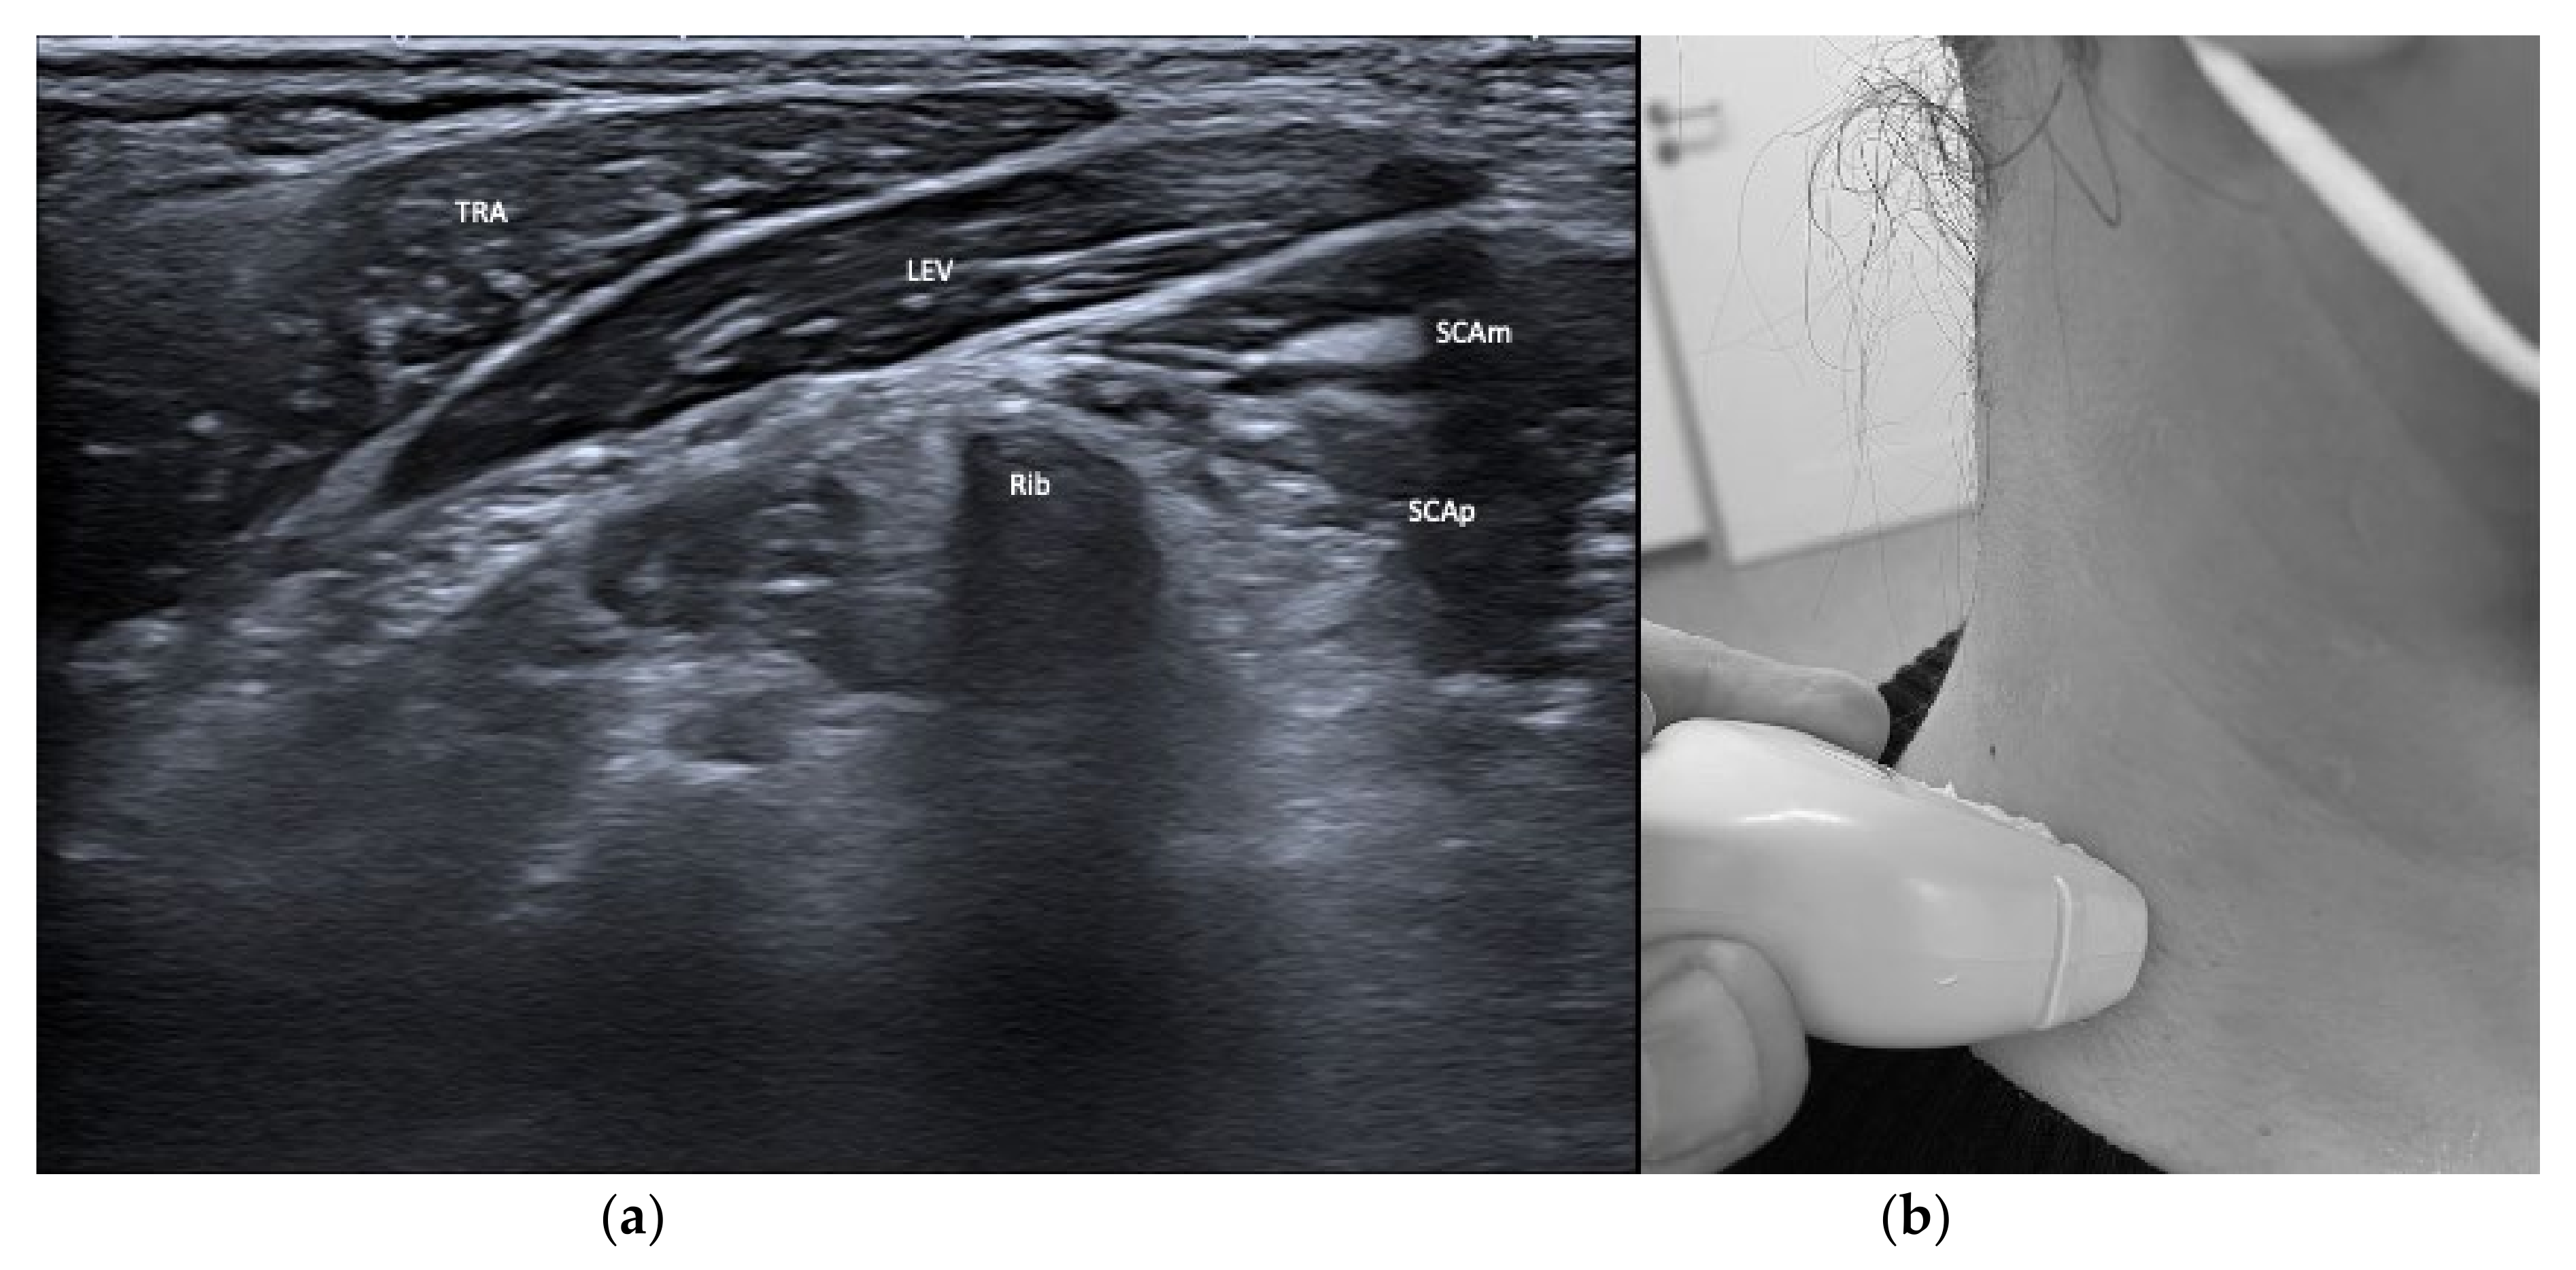

| Splenius cervicis (SPLcer) | Ipsiversion of neck | +++ | ++ | LEV, TRA, Longissimus cervicis | Relevant for full turn of the neck |

| Trapezius (TRA) | Extension of neck | + | + | LEV, Supraspinatus | |

| Levator scapulae (LEV) | Lift of scapula | + | + | SPLcer, TRA | |

3.4. Safety Issues and Imaging of Relevant Neighboring Structures